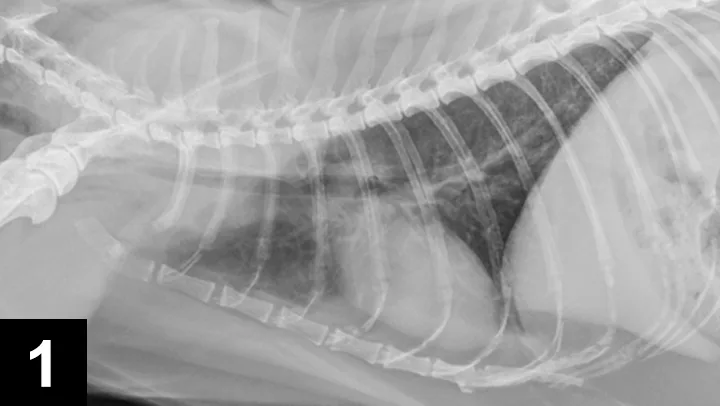

Figure 1. Thoracic radiographs performed on a cat with mixed respiratory signs. Moderate bronchial and mild unstructured interstitial pulmonary patterns consistent with nondescript chronic airway disease and age-related changes can be observed.

Radiographs remain the most widely available screening modality for identification of tracheal neoplasia.7,9,10 Air provides an excellent natural contrast medium for diagnosis of tracheal masses. Cats with tracheal tumors may have concurrent lung pathology. Thus, the presence of lower respiratory disease should not preclude evaluation for tracheal tumors if clinical suspicion exists. Failure to pursue additional imaging, including cervical and thoracic radiographs, may lead to a misdiagnosis or delay in therapy (Figures 1 and 2).